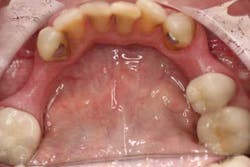

After a complete assessment, it was apparent that Sara’s options were limited with her existing dentition. The caries present were large and apple-cored around the teeth, making the long-term restorative prognosis questionable or guarded at best (figures 2-5). Several key teeth for partial abutments were either missing or grossly carious.